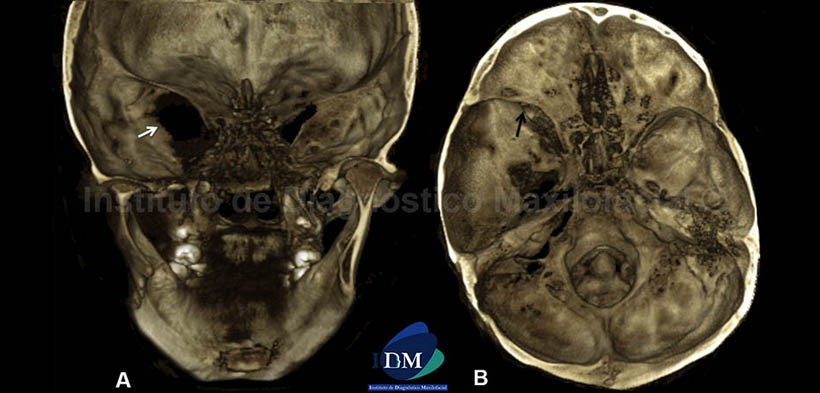

En las vistas tridimensionales se aprecian imágenes comparativas de ambos lados de la mandíbula, tanto en planos superficiales como profundos, los cuales muestran los signos descritos en los cortes anteriores. Se observa el conducto dentario inferior del lado derecho (Fig.6) junto con su conducto accesorio; y en el lado izquierdo (Fig.7), se observa el aumento del calibre del conducto dentario inferior y la mencionada alteración de la morfología del cuerpo, ángulo y rama ascendente. Nótese el severo aplanamiento del cóndilo mandibular.

También se observaron algunos cambios morfológicos en la base craneal media (Fig.8), desde una vista posterior (A) se evidencia la elevación del ala menor del hueso esfenoides y la alteración en la forma del ala mayor, la cual condiciona el aumento de las dimensiones de la hendidura esfenoidal y del agujero óptico del lado izquierdo (flecha blanca), los cuales se ven severamente afectados por el probable origen de una lesión tumoral a ese nivel. Nótese la asimetría de ambas ramas mandibulares desde una vista posterior. Además, en la vista axial (B) se observa el aumento de tamaño de la fosa craneal media del lado izquierdo condicionada por la displasia del ala mayor del esfenoides (flecha negra) y la remodelacion de la cortical del hueso temporal.